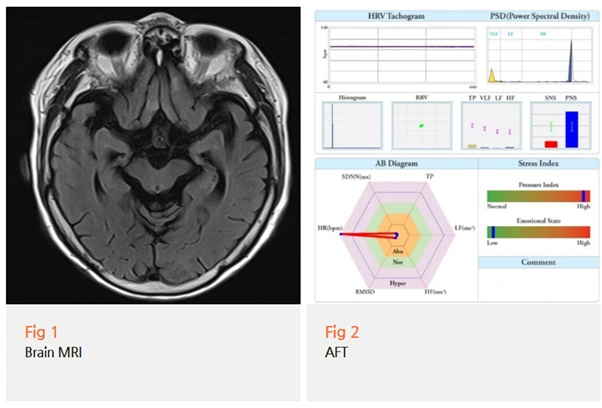

당일 뇌 MRI와 MRA, 인지기능 검사를 받으셨어요.

MMSE 점수가 14점으로 나왔고,

MRI상 뇌위축이 상당히 진행된 소견이 확인되었다는 결과지가 나왔어요.

%EA%B7%B8%EB%A6%BC2.png?type=w966